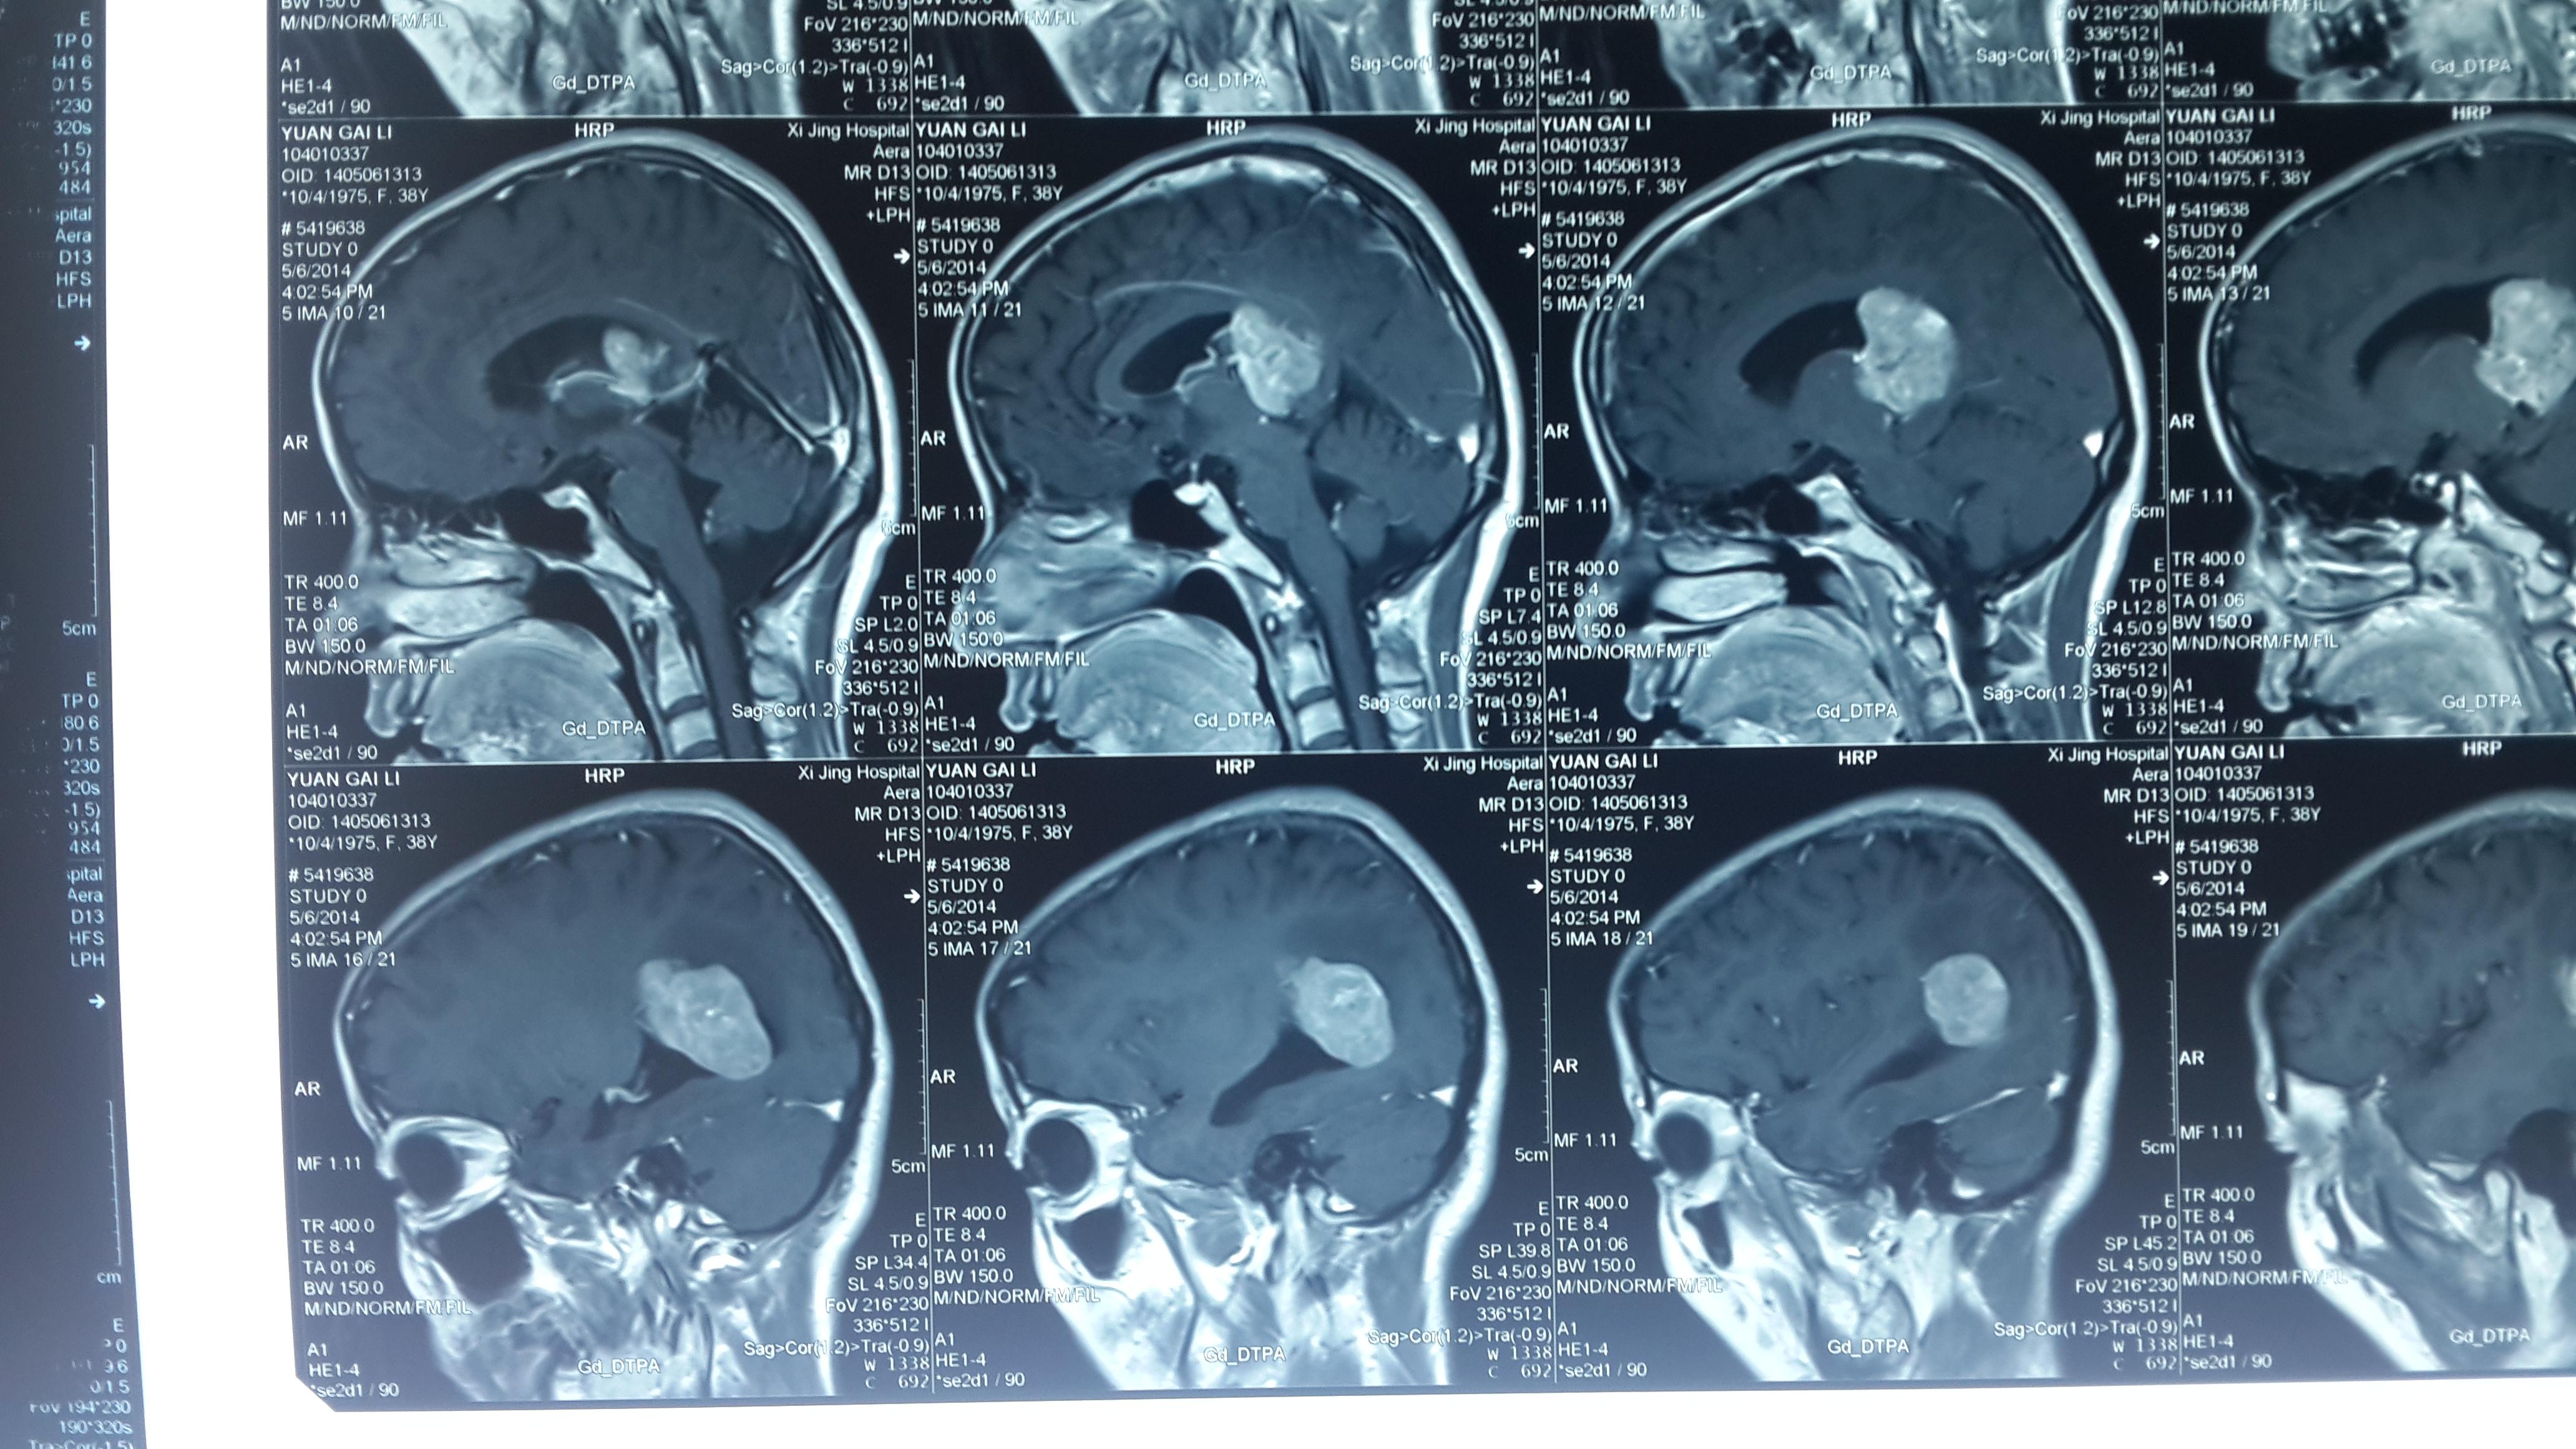

贺晓生教授侧脑室三角区脑膜瘤手术切除

图片尺寸930x523